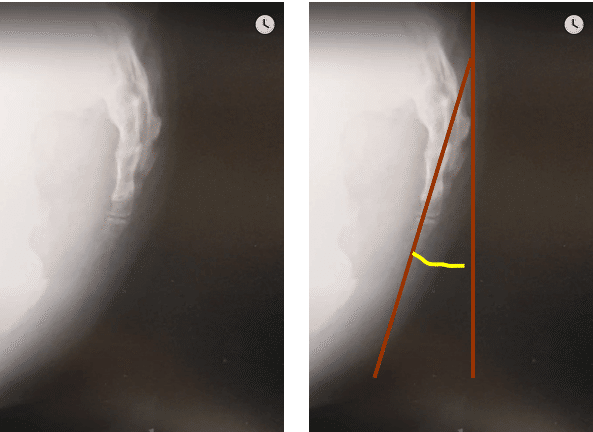

尾てい骨の痛みがある場合、整形外科などで**レントゲン検査(X線検査)**が行われることがあります。レントゲンでは主に、骨折・ひび(不全骨折)・明らかな脱臼や変形といった「骨そのものの異常」が確認対象になります。

特に、転倒して尻もちをついた直後や、強い外力が加わったあとでは、尾てい骨に骨折が起きていないかを確認する目的で撮影されるケースが多いとされています。撮影は正面像や側面像で行われ、尾骨の角度や連なり方を評価します。